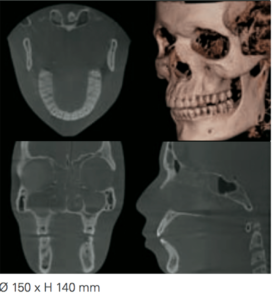

Scan completo

150 x H 140 mm